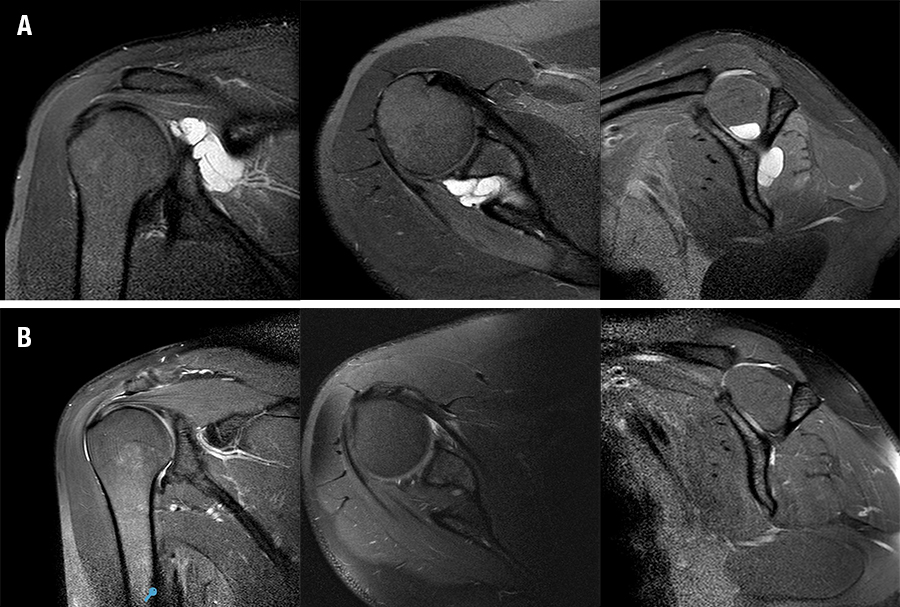

La resolución completa del quiste se evidenció en 20 pacientes (fig. 2). Ningún paciente tuvo recidiva, se observó en un paciente el quiste residual asintomático con un diámetro de 1,3 cm en el plano coronal (escalas finales: Rowe 95 y Constant 90).

Figura 2: Paciente de 32 años con omalgia derecha. A) Imágenes preoperatorias. B) Imágenes de control posoperatorias.